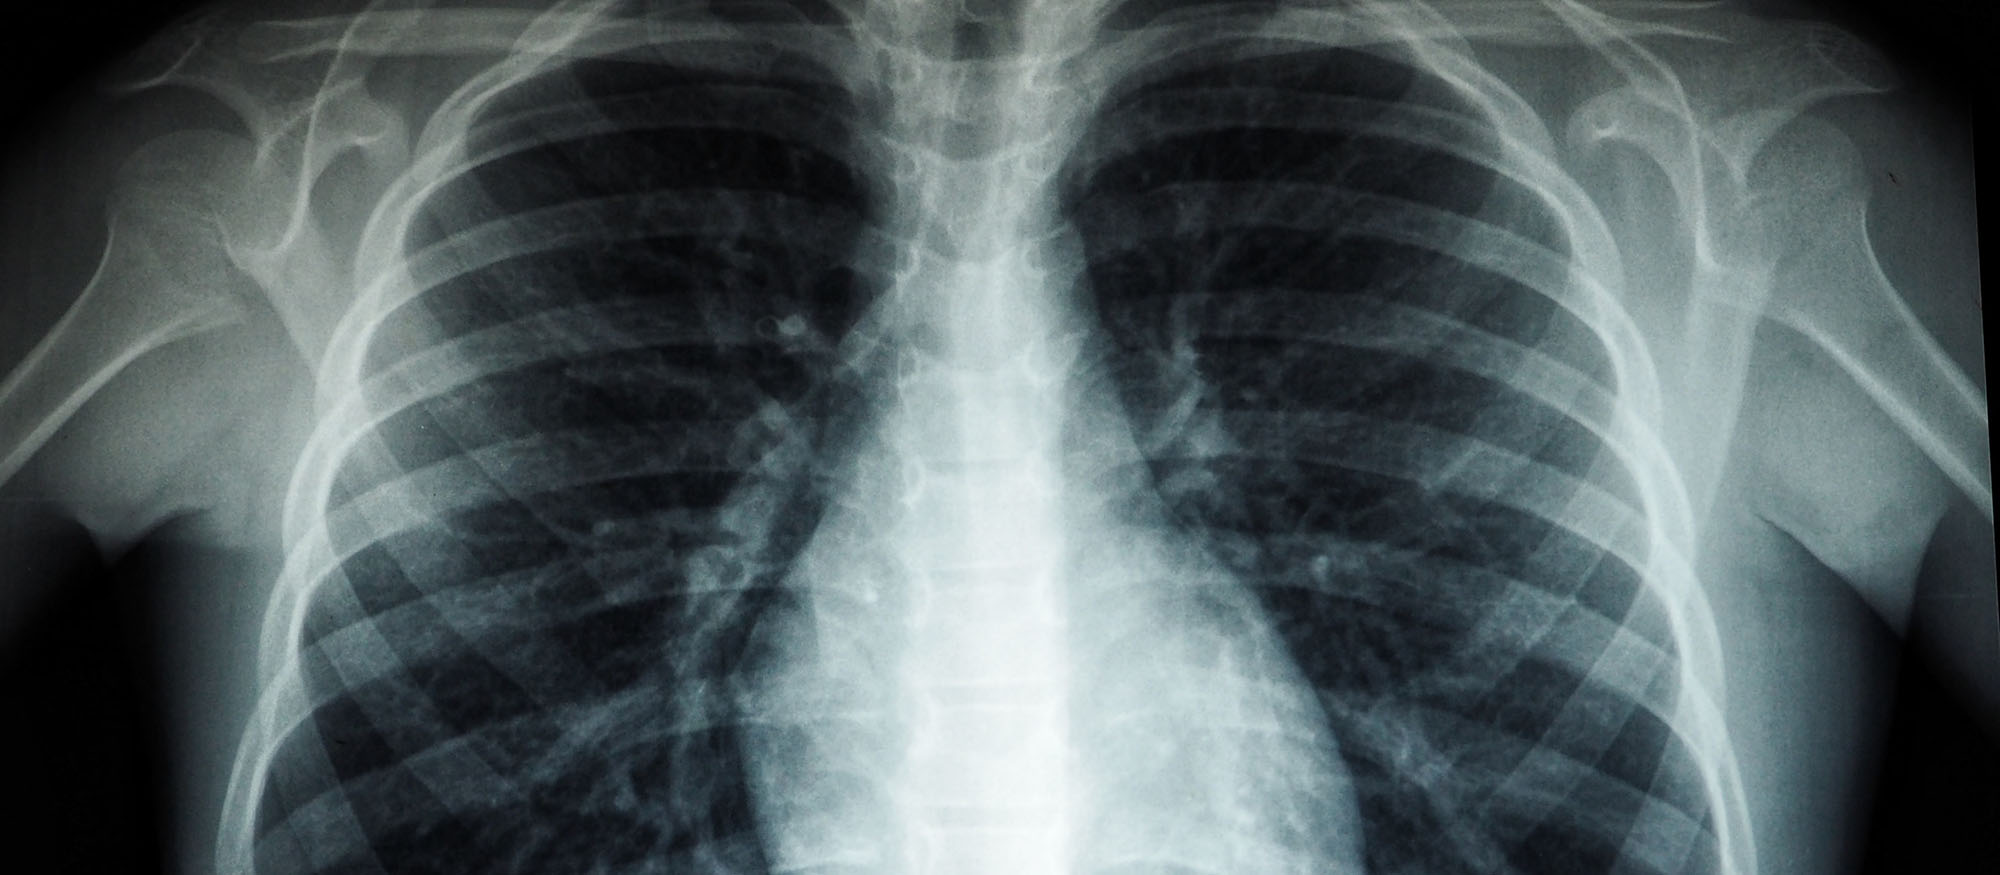

Diagnostic Radiography is a high-tech part of modern healthcare and many patients have some form of medical imaging to diagnose or monitor their condition. This means there is high demand for medical imaging such as X-rays as well as CT, MRI, ultrasound and radioactive trace scans.

You’ll be trained to use cutting edge technology to produce and process images of internal body structures like the bones, blood vessels and organs or provide real-time imaging to guide surgery.